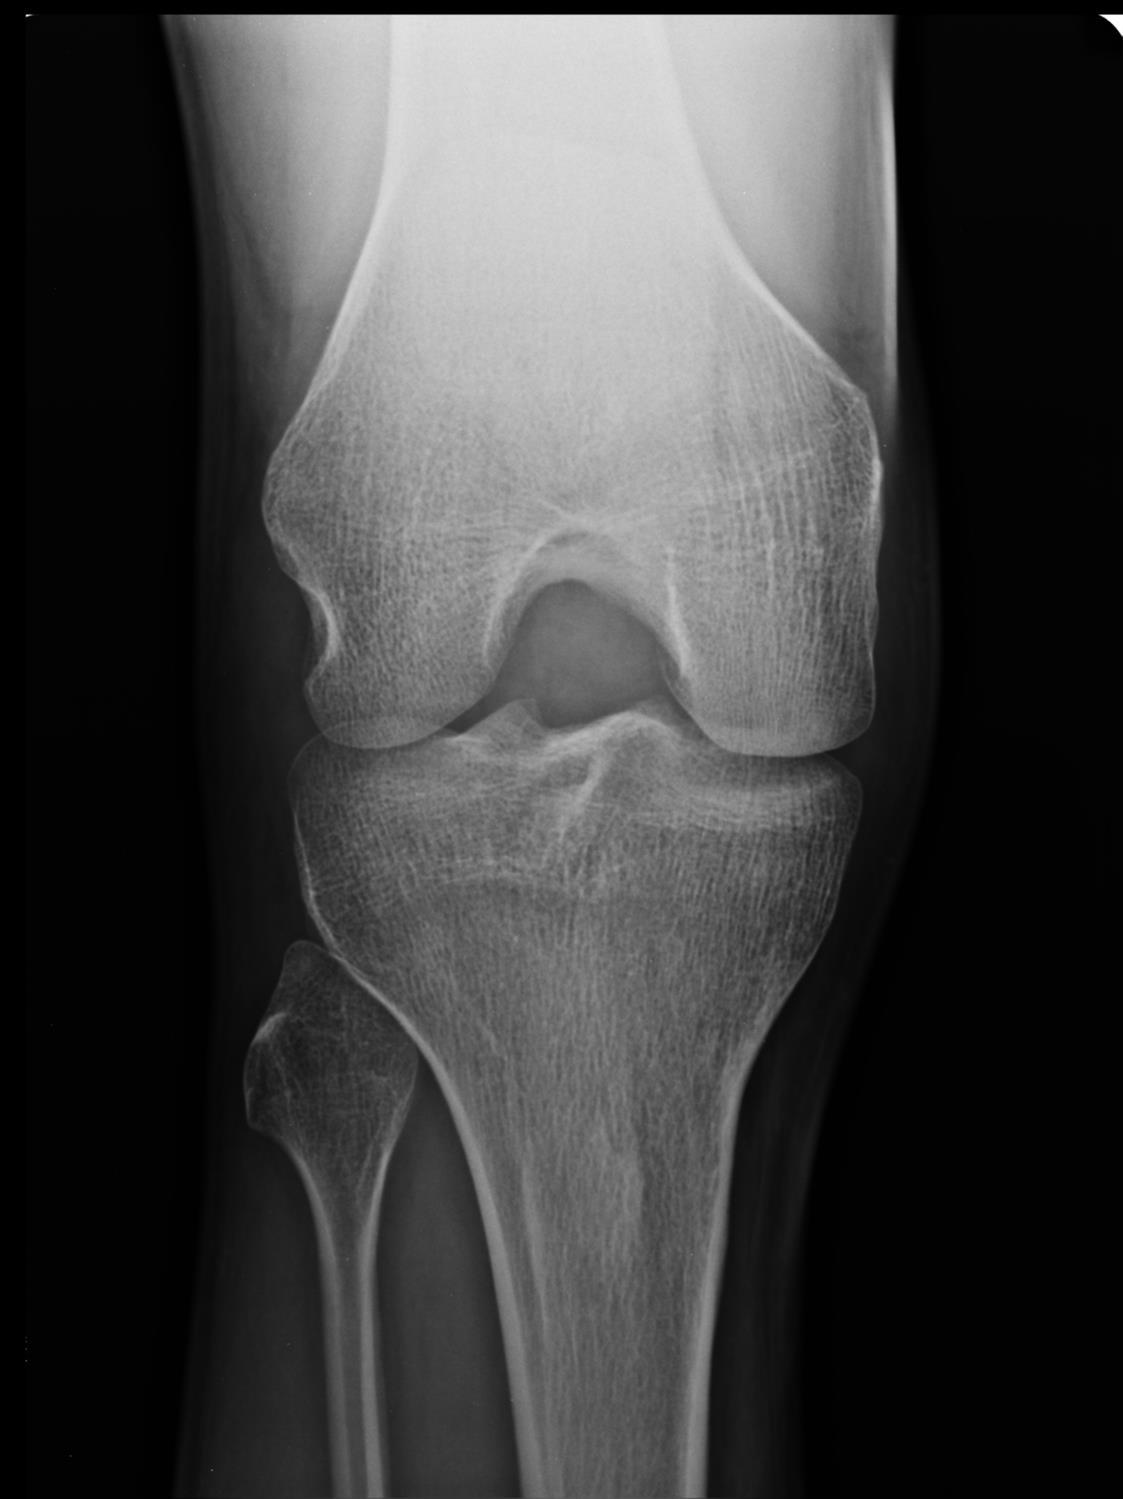

Diagnosis?

Bone Infarct